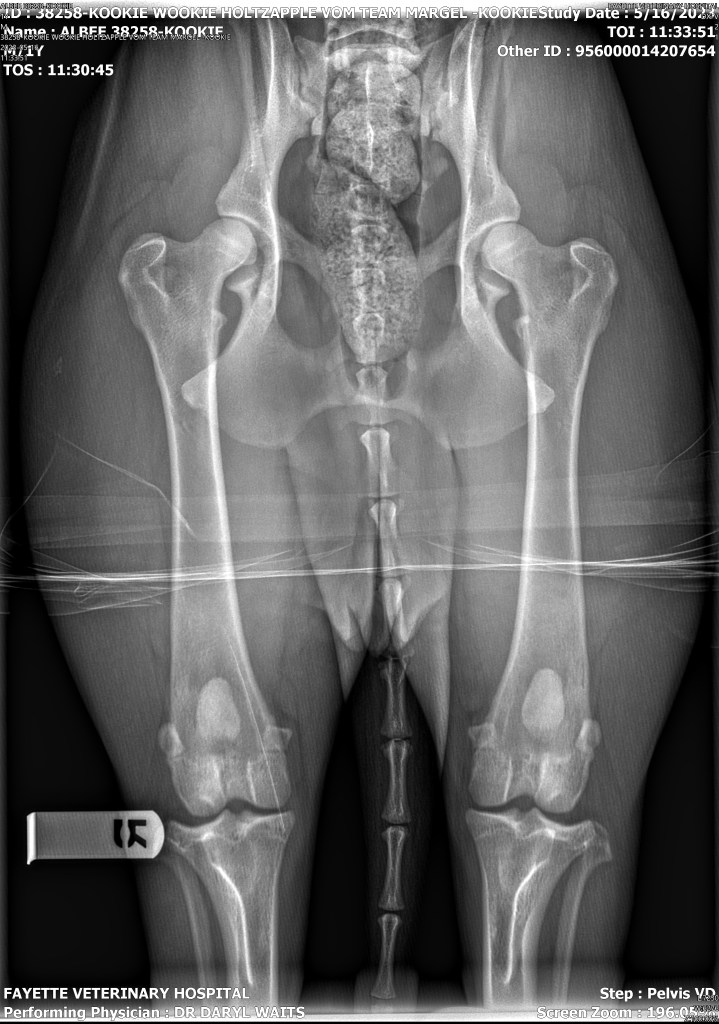

*DOB: 1-26-2022 *Black and red long coat female *73 pounds *Parents- Raja x Oonyx *OFA prelim elbows- Good *Pennhip R-0.37 L- 0.21 Canine Healthcheck full panel- clear